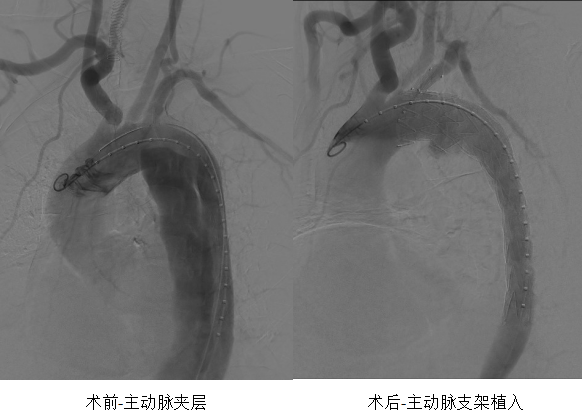

CT室接到电话通知后迅速响应,准备工作一气呵成,从患者进入CT室到完成检查,全程不到10分钟。CT室医生张佳甚紧盯屏幕,第一时间作出精准诊断:“Standford B型主动脉夹层”。

介入血管科主任余景志在接到电话后,顶着风雨第一时间赶到医院。在仔细查阅患者的影像资料后,他果断拍板:“具备急诊手术指征,立刻激活介入团队!”同时,他向麻醉科发出紧急支援请求:“需要一位有经验的麻醉医师,术中必须平稳控制血压!”

一切准备就绪,患者被平稳送入介入手术室。此刻,介入血管科主任余景志、医生沈盼、李江,护士长龚明霞、护士文怡,以及麻醉医师刘露早已严阵以待。手术台上,大家配合默契,操作精准;麻醉医师刘露紧盯监护仪,将患者血压维持在理想状态。从麻醉开始到手术结束,整个过程仅用时1小时30分钟,这颗随时可能“引爆”的“血管炸弹”被成功拆除。